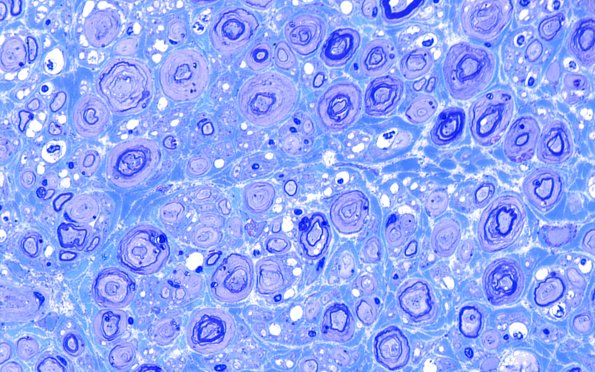

Washington University Experience | PERIPHERAL NEUROPATHY | 0 PNS ARTIFACTS | 18G1 Vesicular Myelin Change Artifact Plastic 100X 3

18G1-3 In this case a number of small myelinated axons are also involved by vesicular myelin artifact.